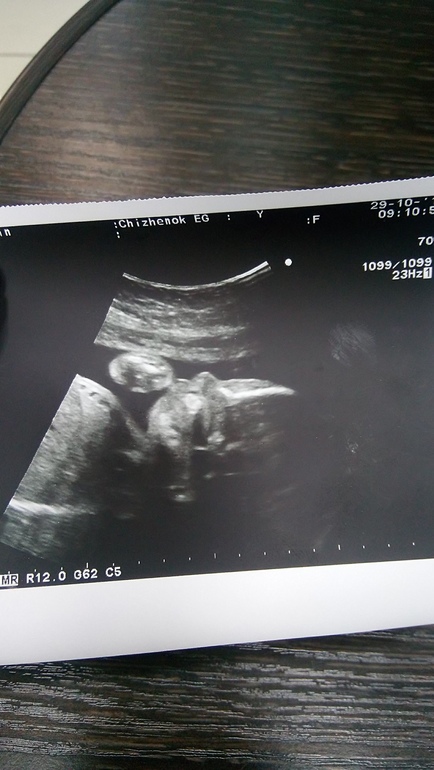

Узи в 24.3 недельки и обо мне

УЗИ, КТГ, доплерПодтвердили мальчика и крепенького, вес 840 г, превышает....как и первый малыш будет крупным. сделала фотки..такой хорошенький)))пальчик сосал)) сказала, что такими темпами,нужно будет на роды ложиться раньше, тем более плановое кесарево. Сегодня вспомнили, что врачи хотели прерывать б в начале и посмеялись, хорошо что мне попалась она (узистка), вернее я сама её нашла,она мне первого малыша спасла. в общем, все хорошо у него.